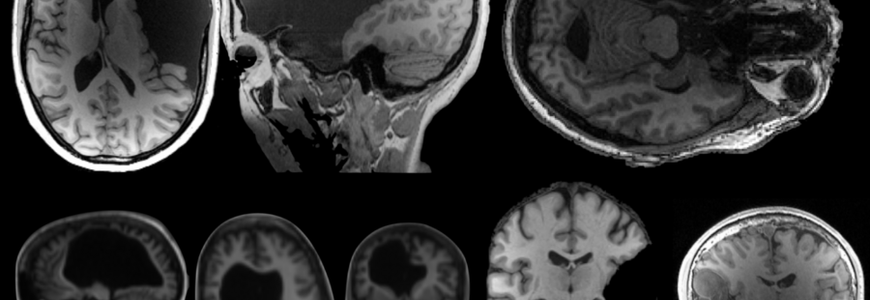

Dr. Fedorenko's lab specializes in unusual language-related brain adaptations and capacities. She discusses a case of first language acquisition despite the absence of the left temporal lobe, a brain region necessary for language development and processing. In this case, the right brain compensated for the missing left brain region. And the child proved exceptional in language skill. Dr. Fedorenko also describes other cases in her lab's Interesting Brains Project.

Looking under the hood at the brain’s language system